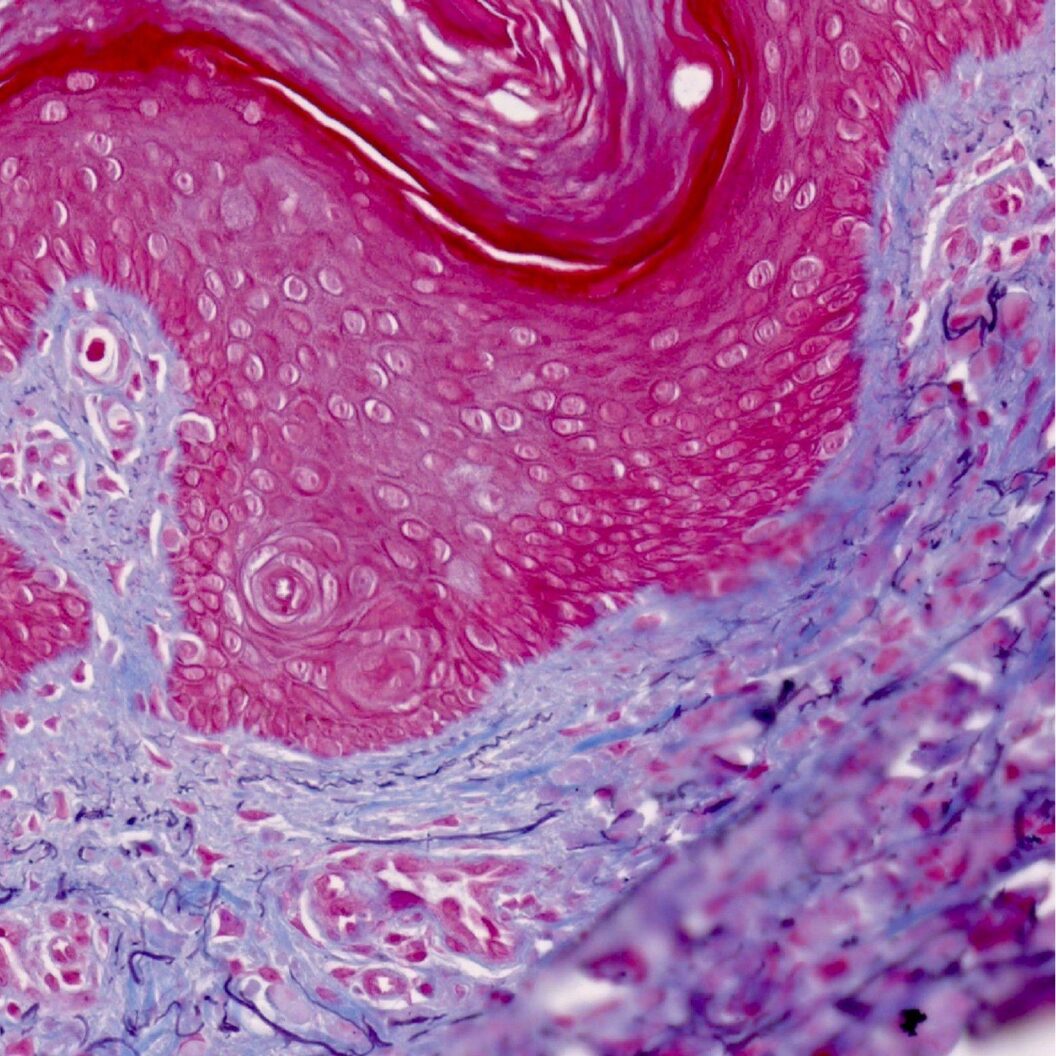

Kevin Mackenzie, University of Aberdeen. Dermatofibroma, LM. n.d. Part of Open: Wellcome Collection, Artstor.